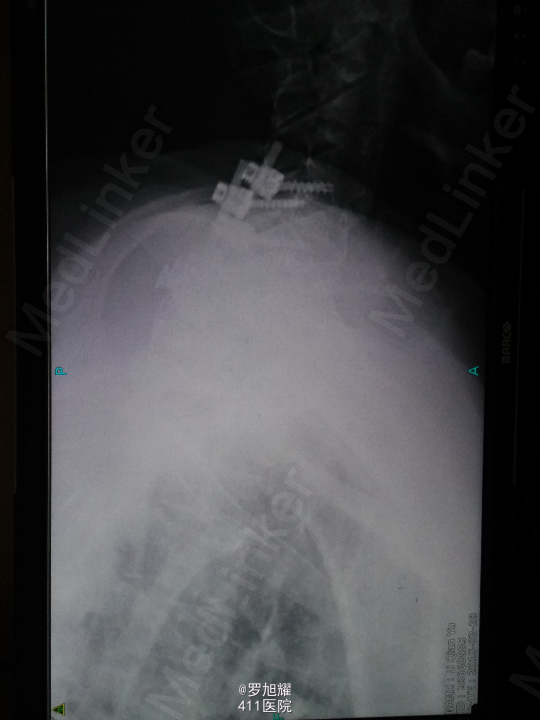

查体:双上肢前臂及以远感觉丧失,躯体自第二肋间平面以下感觉丧失。耸肩可,双侧三角肌、肱二三头肌肌力2级,腕关节屈伸、旋转及各指肌力0级。腱反射阴性,但球海绵体反射已经阳性。影像学检查示颈椎骨折脱位伴颈髓损伤。

诊断:颈6/7骨折脱位伴高位截瘫。处理:立即甲强龙冲击、脱水、保胃、营养神经治疗。首选治疗方案是颅骨牵引复位后前路融合固定,较后路稳定,出血也少,和家属谈话后开始颅骨牵引复位,4kg起步,每半小时增加1kg直至14kg,调整颈椎屈伸位,再加用手法牵引仍不能复位。改用备选方案,急诊行后路切开减压撬拨复位内固定,术后瘫痪症状部分改善。随访3月双上肢前臂及手部感觉恢复,仅双手掌尺侧及小指感觉障碍,双侧三角肌、肱二三头肌肌力4-5级,腕关节屈伸、旋转肌力左侧3级,右侧3-4级,但各指肌力仍0级。